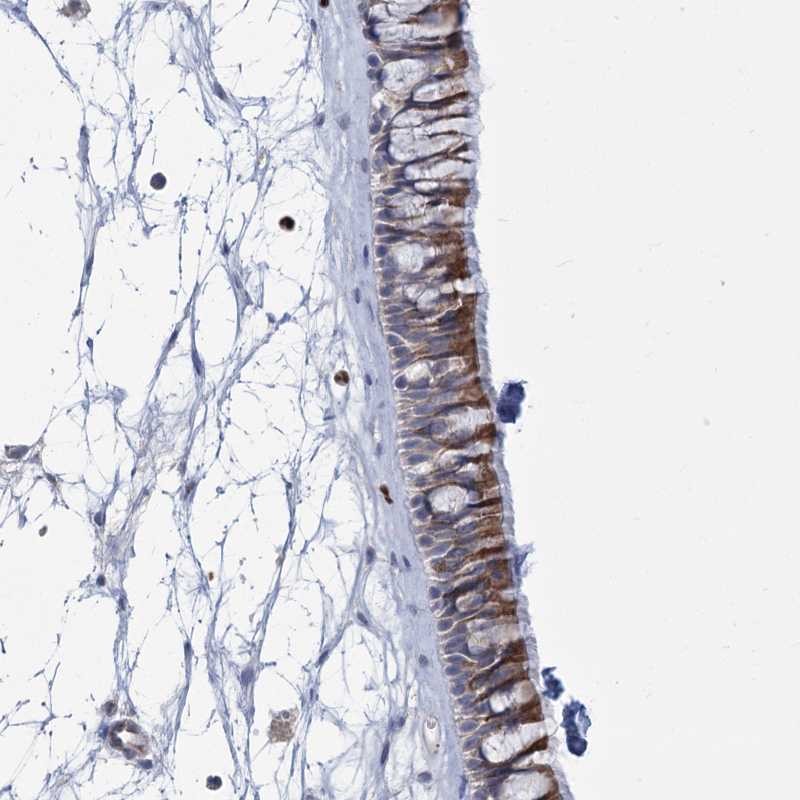

Immunohistochemical staining of human nasopharynx shows moderate cytoplasmic positivity in respiratory epithelial cells.